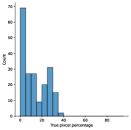

A few sample images and the corresponding masks of the polyp dataset in HyperKvasir are shown in Fig 2. The polyp images are RGB images. The masks of the polyp images are single-channel images with white () for true pixels, which represent polyp regions, and black () for false pixels, which represent clean colon or background regions. In this dataset, there are different sizes of polyps. The distribution of polyp sizes as a percentage of the full image size is presented in the histogram plot in Fig 3, and we can observe that there are more relatively small polyps compared to larger polyps. Additionally, a subset of this dataset was used to prove that the performance of segmentation models trained with small datasets can be improved using our SinGAN-Seg pipeline, and the whole dataset was used to show the effect of using SinGAN-Seg generated synthetic images instead of a large dataset which has enough data to train segmentation models. In this regard, this dataset was used for two purposes:

To understand the difference between the mask distribution of real images and synthetic images, we plotted pixel distribution of masks of synthetic images in Fig 6. This plot is comparable to the pixel distribution presented in Fig 3. The randomness of the generations made differences in the distribution of true pixel percentages compared to the true pixel distribution of real masks of real images. However, the overall shape of synthetic data mask distribution shows a more or less similar distribution pattern to the real true pixel percentage distribution.